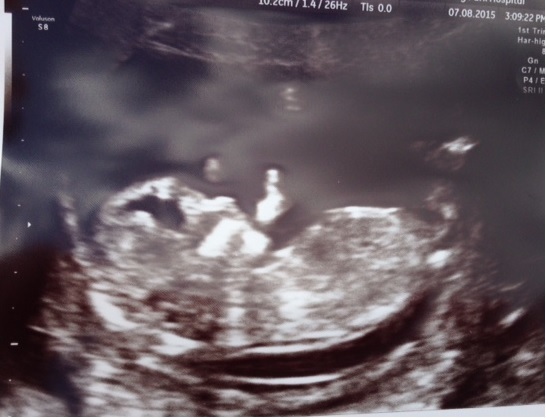

anyway just popped in to say the scan on Friday went really well, was an incredible experience and everything looks just perfect :)

feels very real now and for the first time I am excited about becoming a mum!